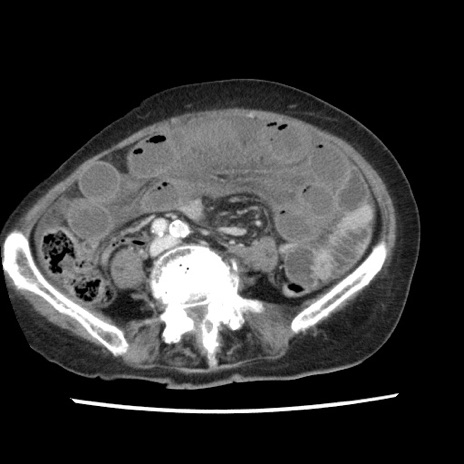

症例1(横断像)

【症例】80歳代女性

【主訴】腹痛

【現病歴】8時間前から腹痛あり来院。

【既往歴】糖尿病、脂質異常症、子宮体癌にて子宮全摘術

【身体所見】意識清明・会話良好だが腹痛で苦悶様、全腹部にわたって反跳痛と圧痛あり

【データ】WBC 13600、CRP 0.14、LDH 224、CK 90